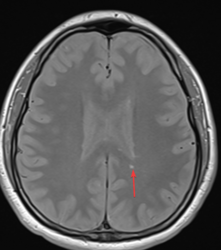

@nezka92 zdjęć, na których widać, że jest wszystko ok, mam kilka (i to jest jedno z nich). Z innej perspektywy są pewne widoczne zmiany, których być nie powinno. Celem leczenia jest opóźnienie, a najlepiej całkowite zatrzymanie postępu, czyli pojawiania się nowych zmian w mózgu. Nie ma w tej chwili sposobu, aby takie zmiany już powstałe, wyleczyć. Gdyby zaczęły pojawiać się nowe to z pewnością odczułbym to np. zmianą temperatury skóry, jakimś niedowładem w ręce/nodze. Nigdy tak nie miałem i obym nie miał

A tak poza tym to jeszcze rozwinę trochę temat samego SM. W okół tego badziewia narosło wiele mitów, bo kojarzy się to głównie tylko z wózkiem. Kiedyś tak było, bo nie było dobrej diagnostyki i to stawiano tylko ludziom, którzy mają naprawdę widoczne ubytki neurologiczne. Teraz się w miarę szybko wykrywa no i leczy. Łażąc do szpitala co 3 miesiące poznałem sporo ludzi, którzy z tym żyją wiele lat i funkcjonują całkowicie normalnie. I nie jest to aż tak rzadka przypadłość, bo w Polsce żyje z tym 50k ludzi, a pewnie jest jeszcze więcej, bo ludzie po prostu przechodzą to naprawdę łagodnie (tak jak np. ja).